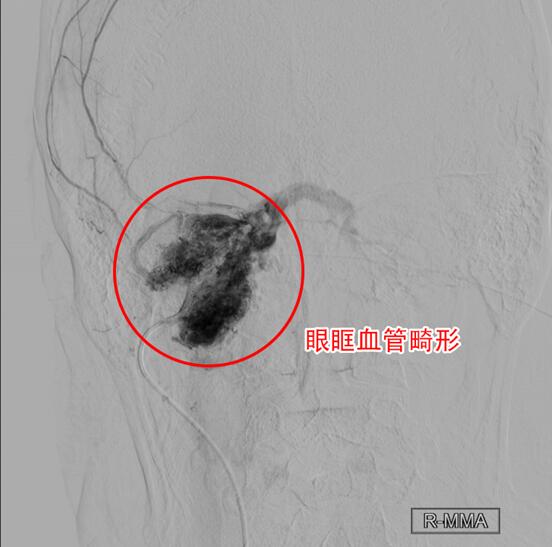

从发病起始到现在,孙伟开始漫漫十年求医路,辗转十多家名医院,不少疗法也都用了,但“眼疾”却越来越重。幸运的是,孙伟这次诊疗总算找对了人。在首都医科大学三博脑科医院导管室,神经介入科主任刘加春对其“眼疾”进行了介入治疗,揪出了潜伏十年的真凶——眼眶血管畸形。祛除了病灶,十年的眼眶浮肿终于消下去了,同时右眼的视力没有受到任何影响。目前,孙伟已康复出院。

眼疾不能再拖,再拖视力可能会受到不可逆的损害。2017年11月,孙伟又一次北上进京,寻找知名眼科专家就诊。检查右眼超声显示:右眼下方肌外直肌肌锥间内团状血管结构。后又经核磁显示,右侧眼球向外突出,其眼眶内、眶周软组织内弥漫性不均质异常信号。这一次眼科专家给出了不一样的诊疗结果,考虑为右眶内动静脉畸形。孙伟不放心又去上海、广州等知名医院就诊,都给出了同样的答案。明确了病灶,但孙伟的求医路仍不顺畅。在接下来的一年多,孙伟又经历的一次次的求医挫折。

确诊了眼眶血管畸形,但治疗却犯了难。由于血管畸形的药物治疗方面作用有限,手术切除或介入治疗是***。但由于孙伟的畸形血管团已经完全充满在眼眶内,血流量高,众多供血动脉交错,直接开刀手术风险极大,很有可能术中大出血,导致丧失视力等严重后遗症。超声介入单纯地注射硬化剂精准度稍差,术中很可能会导致失明。辗转几家知名医院,眼科医生都对手术方案迟迟定不下来。

刘加春主任介绍,传统的外科对表浅的,范围小的眼眶血管畸形可行手术切除,但范围大,或大面积的血管畸形时,手术治疗难度大,有切除不完全、失血量大等危险。血管内栓塞治疗技术告别了大出血、非特异性损伤、解剖视野差、切除难等手术难题。同时相比于单纯的注射硬化剂治疗,通过血管造影,可以了解动静脉之间异常交通的形状、部位、病变范围和周围血管的关系,进行精准的栓塞治疗,做到“有的放胶”。

2月18日,借助血管造影,刘加春主任在X线透视下,一边观察屏幕上迂曲、密集的血管走向,一边在距离大脑1米多的大腿股动脉操控导管,将导管顺着血管准确地送达眼眶内畸形血管团。为保护夹杂在的畸形血管团中的视网膜中央动脉不受伤害,刘加春主任分别从畸形团的不同方位,经眶下动脉、脑膜中动脉等三个动脉入口,环绕注射外科胶栓塞。经过近3小时的手术治疗,右眼眶内血管畸形绝大部分被栓塞,更重要的孙伟的视力没有受到任何影响。术后,孙伟浮肿的眼眶一天天地消除下去,目前已经康复出院。